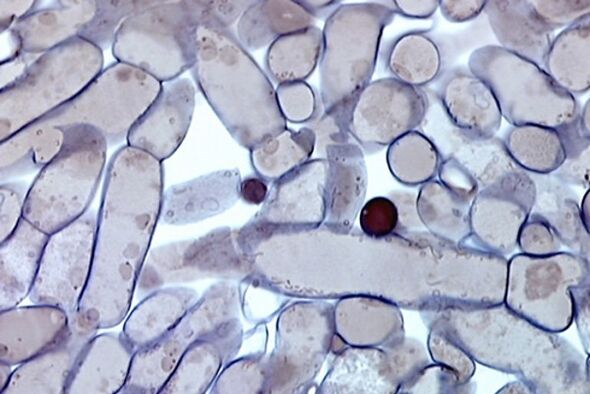

Mikozun tezahürü, topuklarda ve ayaklarda artan kuruluk ve pullanma ile başlar. Bazen şiddetli kaşıntı, kabarcık ve mısır oluşumu ile birlikte kızarıklık görülür. Aşırı terleme sorunu yaşayan kişilerde bebek bezinde pişik meydana gelir. Tırnak yapısını ve rengini değiştirerek sararır ve çatlar. Sporlar plakanın derinliklerine nüfuz ettiğinde, altında boşluklar oluşur, ufalanan bir karışımla doldurulur ve hoş olmayan, paslandırıcı bir koku oluşur.